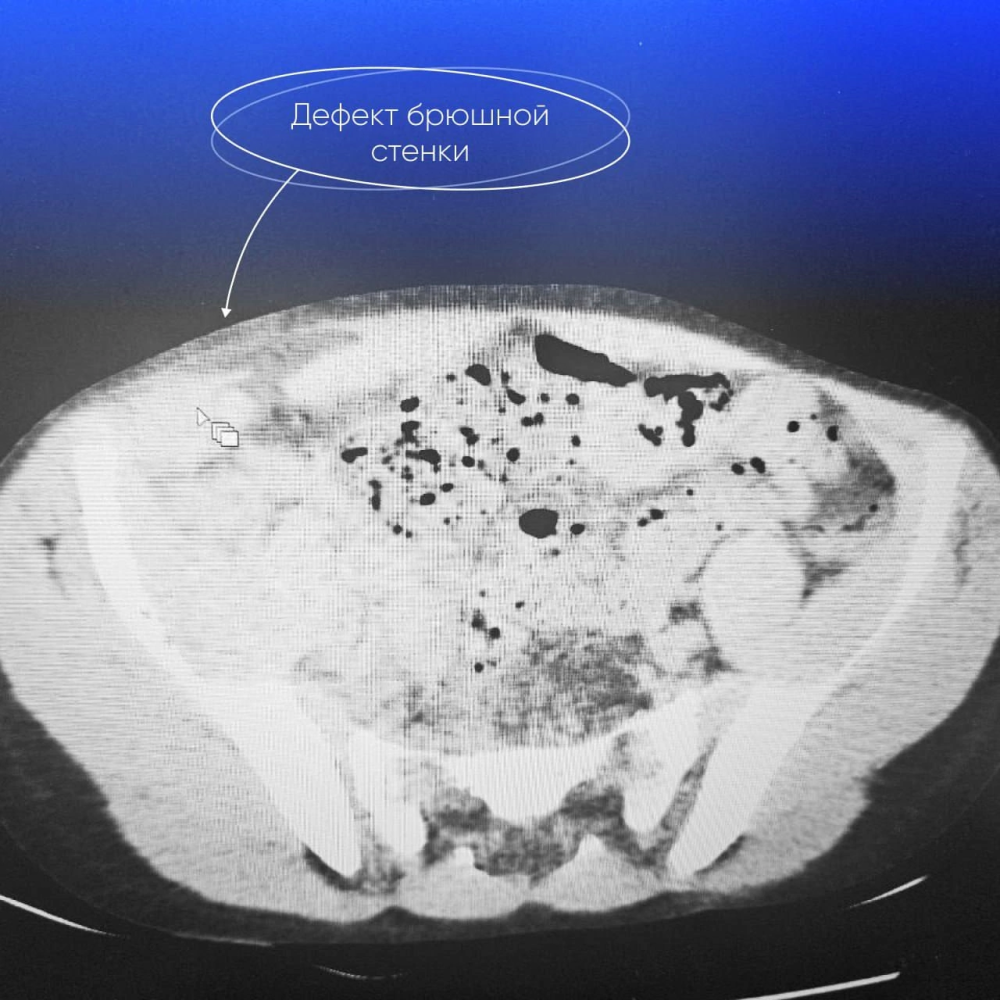

«24 июня в приемное отделение был доставлен 10-летний мальчик с травмой живота — он упал на скорости с велосипеда. При осмотре дежурный хирург Андрей Федорович Михайлов выявил дефект передней брюшной стенки до 6 см в правой подвздошной области. Через него подкожно определялись петли кишечника», - описал случай глава окружного департамента здравоохранения. Он отметил, что ранее подобных травм здесь не встречали.

Несмотря на то, что УЗИ показало отсутствие свободной жидкости в животе, а компьютерная томография не выявила костных повреждений и травм внутренних органов, характер дефекта требовал немедленного хирургического вмешательства.

В экстренном порядке врачи приступили к операции. В ходе вмешательства был обнаружен разрыв мышц брюшной стенки. В подкожной ране визуализировался аппендикс с признаками ушиба и гематомой в брыжейке. Врачи Югорской городской больницы провели аппендэктомию и ушили дефект брюшной стенки. Через 7 дней выздоровевшего мальчика выписали домой.